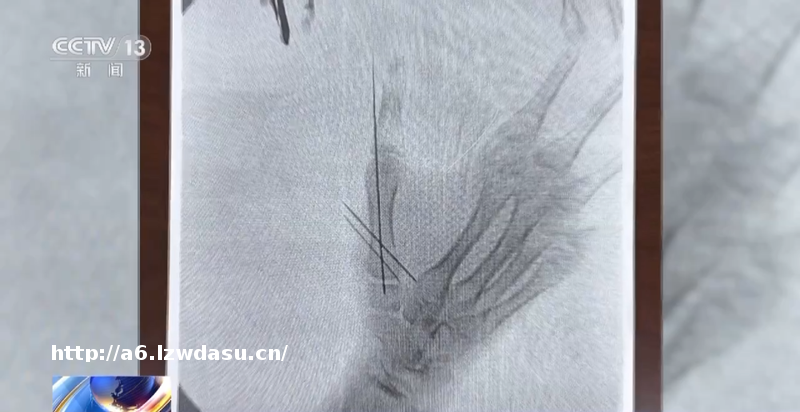

这个房间很小,小黄将双臂向两侧伸直,就可以一只手抵住墙壁,一只手抵住房门,阻止扮演“电锯狂魔”的工作人员进入房间。但正是在这个过程中小黄手骨折了。在游戏结束后,小黄自己联系了家长,说自己受伤了。

原告父亲 黄先生:事发当天其实很突然,我和他妈妈还在外面,然后得到这个消息,说孩子受伤了,后来就一起去医院做了些检查,当时医生说蛮严重的。如果当时我们的孩子,因为害怕没有跟我们说这个情况的话,如果是第二天才去医院**的话,很可能就是留下**的残疾。